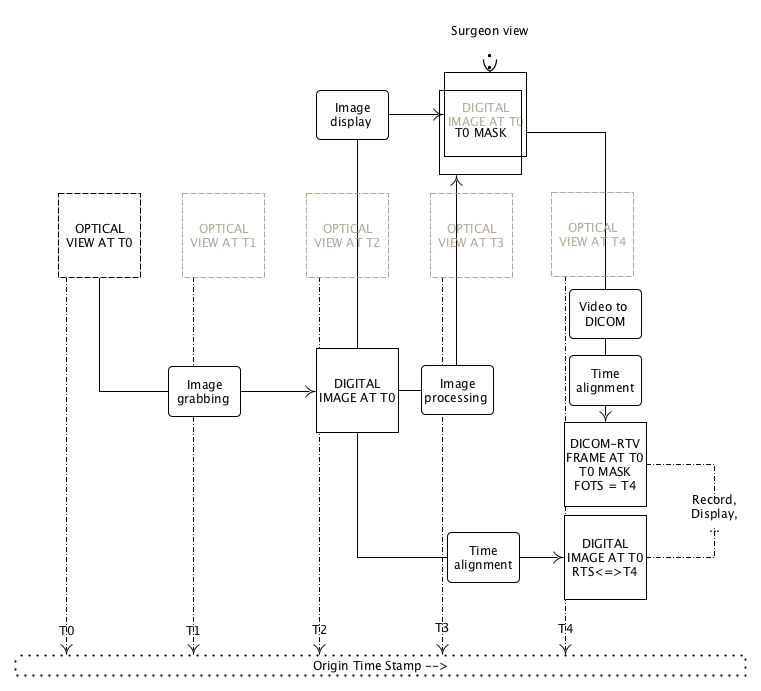

- PPPP.7. Example of DICOM Real-Time Video Implementation

- PPPP.8. Storage Considerationa

- PPPP.9. Example of Engineering Implementation

- PPPP.20. Transmitting a Stereo Video